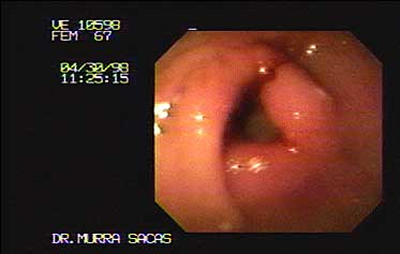

Femenino de 67 años con neoplasia del antro pre pilorico.